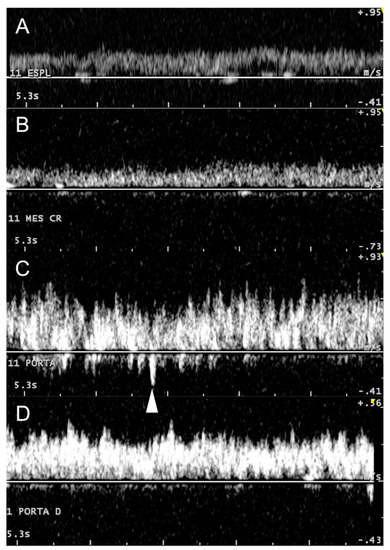

3.2. Portal System

3.3. Caudal Vena Cava and Hepatic Veins